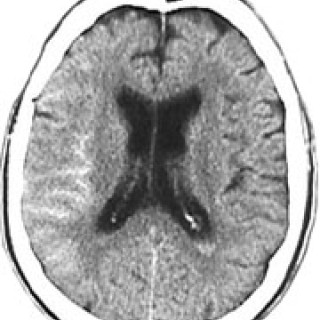

Afrikansk trypanosomiasis, som har meningoencefalitt som endestadium, er en parasittsykdom som overføres fra dyr til mennesker med tsetsefluer. I Vest-Afrika, hvor sykdommen skyldes parasitten Trypanosoma brucei gambiense, har sykdommen ofte et langsomt progredierende forløp, mens sykdommen gjerne har et akutt forløp i østlige deler av Afrika, hvor Trypanosoma brucei rhodesiense er årsaken. Figur 1 viser utbredelsen av trypanosomiasis i Afrika. Selv om det i de senere år av flere grunner har vært økende forekomst av sovesyke i en rekke afrikanske land (1 – 3), har det vært få rapporter om at...